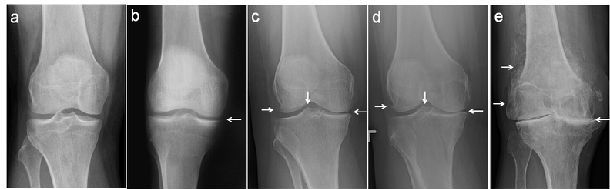

经常会遇到有人发现自己关节疼、肿,到医院拍片,诊断为滑膜炎(图1a,1b)、骨质增生(图1c,1d,1e),还有诊断为关节炎的(图1d,1e)。那到底是那种病?我们对这几种病名分别了解一下。

图1.膝关节的各种X线拍片表现

患者关节肿痛,拍片子后看到报告单上描述的骨质增生,同时观察到X线片上关节(股骨或胫骨)周缘或髁间棘处增生的骨质(图1c,1d,1e左侧和中间白箭头),就断定自己得了骨质增生(有了骨刺)。

从前面我们可以知道,过度活动或年龄增大会造成关节磨损。轻度的关节损伤会造成滑膜炎;重度的关节损伤或年龄增大造成关节磨损会导致退行性骨关节炎,也就是常说的关节炎(图1c,1d,1e)。